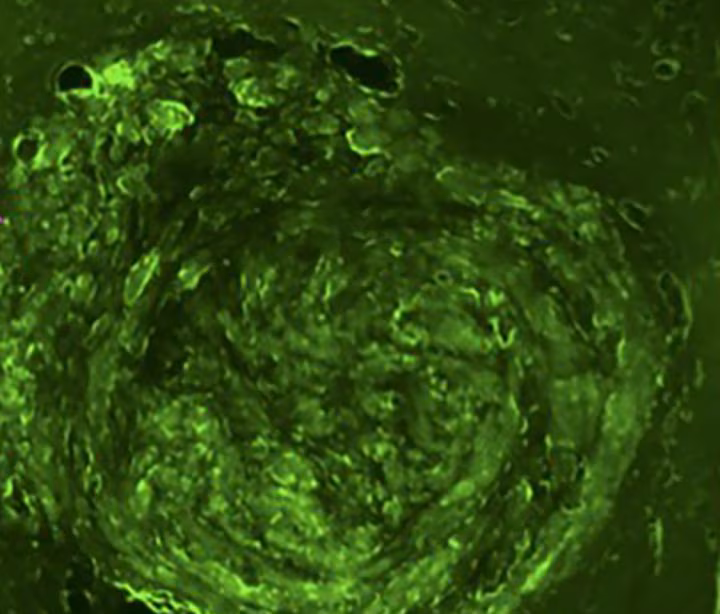

Ph: Washington University in St. Louis

Per provare l’efficacia di questa tecnica sono stati svolte sperimentazioni in un modello murino utilizzando due diversi tipi di glioblastoma. I ricercatori hanno mirato il tumore usando ultrasuoni focalizzati, una tecnica che utilizza l’energia ultrasonica per colpire i tessuti che si trovano in profondità senza dover ricorrere ad incisioni o radiazioni. Similmente a come una lente d’ingrandimento può concentrare la luce solare, gli ultrasuoni focalizzati concentrano l’energia ultrasonica in un punto minuscolo del cervello.

Una volta mirato il tumore cerebrale, i ricercatori hanno iniettato delle microbolle che scorrono attraverso il sangue similmente ai globuli rossi. Quando le microbolle raggiungono il bersaglio scoppiano provocando minuscole rotture della barriera emato-encefalica che consentono ai biomarcatori del tumore cerebrale di passare attraverso la barriera ed essere rilasciati nel flusso sanguigno. In questo modo, grazie ad un’ analisi ematica, è possibile rilevare la quantità di mRNA nel sangue, che fornisce ai medici informazioni specifiche sul tumore. Questo permette di diagnosticare il tumore e facilita la scelta di un trattamento personalizzato.